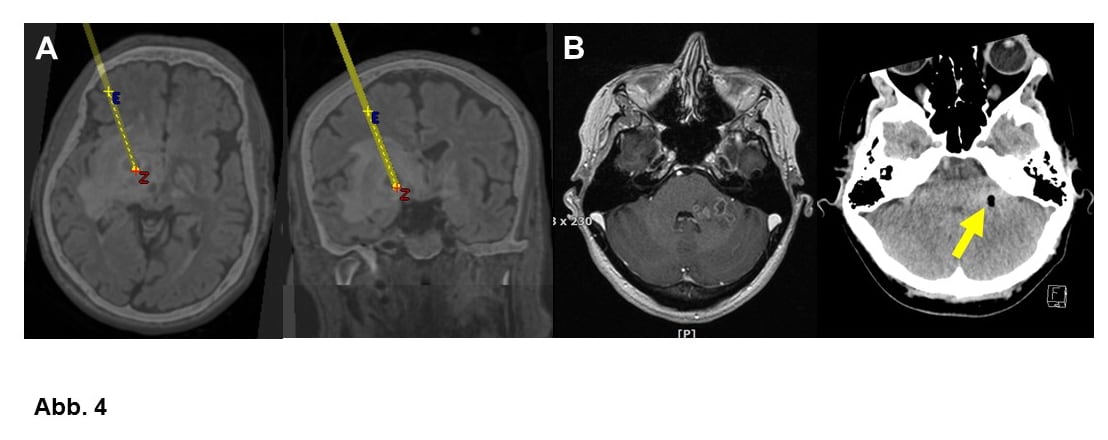

A. Planung einer stereotaktischen Biopsie bei einem tiefgelegenen Glioblastom WHO-Grad IV.

B. Bilder vor und nach (Pfeil: kleines Luftbläschen) einer stereotaktischen Biopsie bei einem Glioblastom WHO-Grad IV, das am Übergang von Kleinhirn und Hirnstamm liegt.